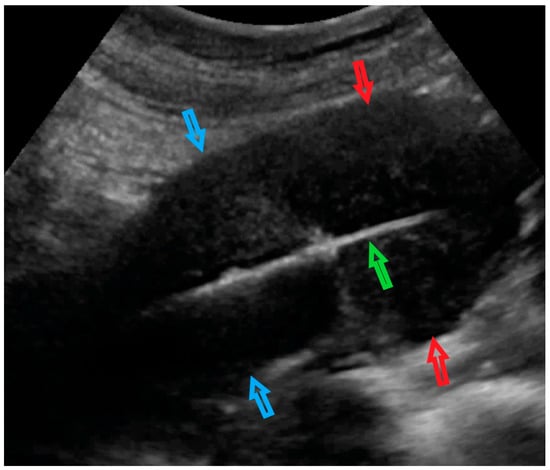

| 4 (56) | Atypical uterine lesion | Figure A4 | Yes | Yes | Leiomyoma (transvaginal ultrasound guided core needle biopsy) | Yes | Leiomyoma and adenomyosis | Yes | No |

| 5 (50) | Atypical uterine lesion (metastatic adenocarcinoma G3 in inguinal lymph node) | Figure A5 | Yes | No | Leiomyoma (UG-TUC core needle biopsy) | No | Uterus / tumor not resected because primary urological carcinoma was diagnosed | Yes | Yes |

| 6 (38) | Atypical uterine lesion | Figure A6 | Yes | No | Leiomyoma, epithelioid variant (UG-TUC core needle biopsy) | Yes (lesion enlarged during follow-up) | Leiomyoma, epithelioid variant | Yes | Yes |

| 7 (29) | Atypical uterine lesion | Figure A7 | Yes | Yes | Leiomyoma (UG-TUC core needle biopsy) | Yes | Leiomyoma with signs of degenerations | Yes | Yes |